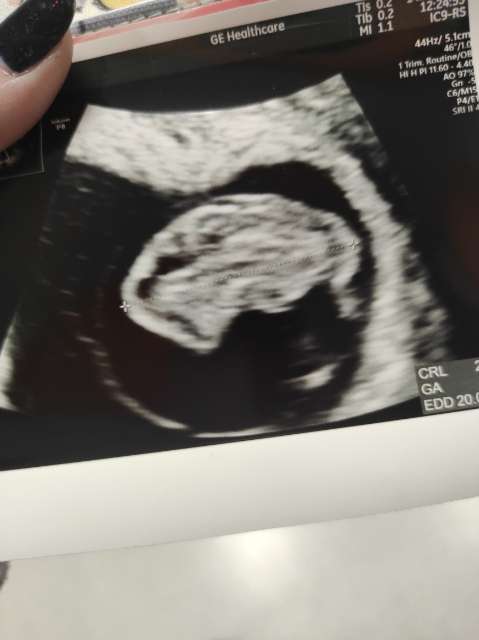

Ja już po wizycie. Wszystko jest okej ❤️ Dostałam skierowanie na prenatalne i dzisiaj będę dzwonić się rejestrować. Kolejna wizyta 4 stycznia

Załączniki

• 3feb46ee-4008-4dc0-a1d8-901d9faaab59.jpg

3feb46ee-4008-4dc0-a1d8-901d9faaab59.jpg

19,8 KB · Wyświetleń: 91